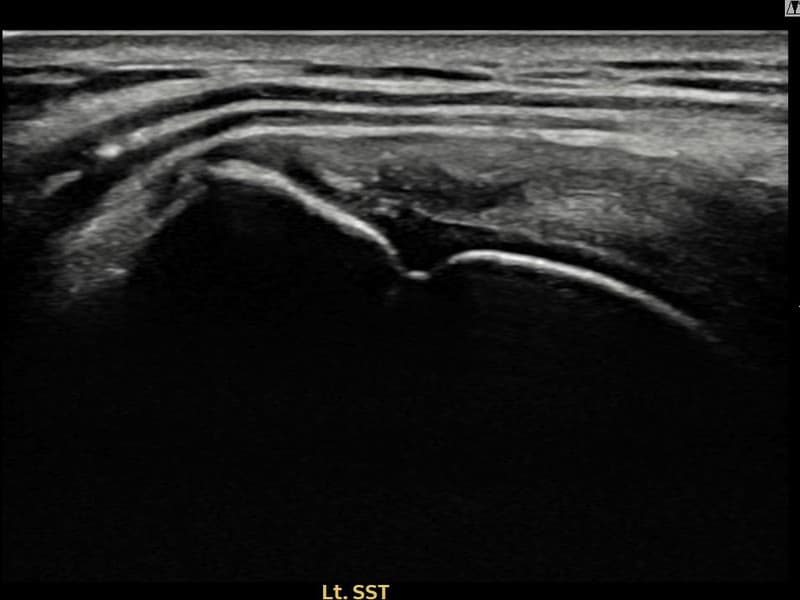

시술 전 초음파 측정 결과 파열 크기는 11mm × 4mm (힘줄 두께의 약 44% 결손)로 확인되었습니다. 시술 전 초음파에서 좌측 극상근건 부착부의 에코 단절과 힘줄 내 결손 소견이 확인되었습니다. 시술 후 초음파에서 부착부 연속성이 회복되고 결손 부위가 재생 조직으로 채워진 것이 관찰되었습니다.

50대 후반 남성 환자분으로, 건설 현장 관리직으로 근무하시며 팔을 자주 들어 올리는 작업을 반복해 오신 분이었습니다. 처음엔 야간에만 통증이 있었으나 점차 팔을 앞으로 올리는 동작 자체가 힘들어져 내원하셨습니다. 초음파 검사에서 좌측 극상근건 부착부의 부분파열이 확인되었으며, 수술 없이 초음파 유도 하 축소봉합술로 치료 가능하다고 판단하였습니다. 시술은 30분 이내에 완료되었고 당일 귀가하셨으며, 이후 단계적으로 재활 운동을 시행하였습니다. 시술 10주 후 추적 초음파에서 극상근건 부착부 연속성이 완전히 회복된 것이 확인되었고, 통증 없이 현장 복귀에 성공하셨습니다.